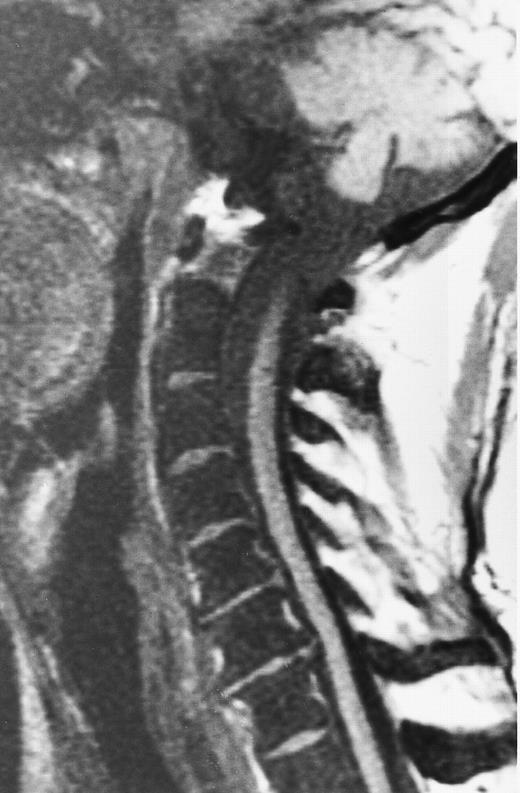

An 8-year-old boy with Burkitt's lymphoma and diffuse marrow involvement. Fat-suppressed, T2-weighted fast spin echo (3000/96, TR/TE) sagittal MR image of the lumbar spine shows heterogeneous signal intensity of the bone marrow and epidural extension of tumor (arrowheads) at the level of L5 and L2, with apparent preservation of the vertebral cortex.